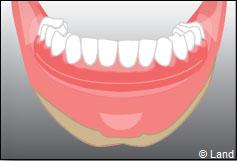

Situation clinique initiale

Les implants peuvent aussi servir à stabiliser un appareil amovible au maxillaire supérieur comme au maxillaire inférieur. Dans ce cas, les implants retiennent la prothèse amovible par des systèmes d’attachement.